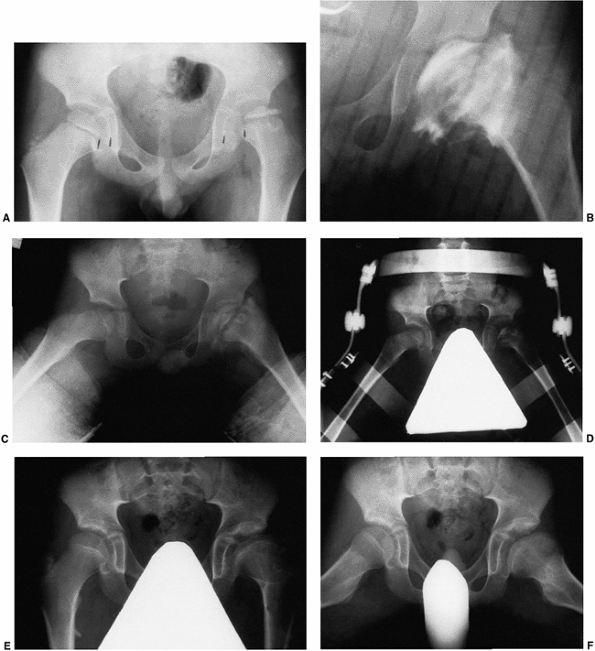

Figure 25.24 A 5-year-old boy with Catterall group 4 disease and at-risk status. A: Anteroposterior radiograph on presentation. B: Anteroposterior arthrogram, in the same position as in C,

after 10 days of traction. Note the relation between the lateral acetabular margin and the lateral margin of the cartilaginous femoral head, as well as the severe flattening of the femoral head. C: Anteroposterior radiogram in Petrie broomstick abduction plasters. The patient was maintained in casts for 6 weeks. D: Anteroposterior radiograph with pelvis abduction orthosis (weight bearing). E: Anteroposterior radiograph at age 13 years. Note residual deformity. F: Lauenstein radiograph at age 13 years. |